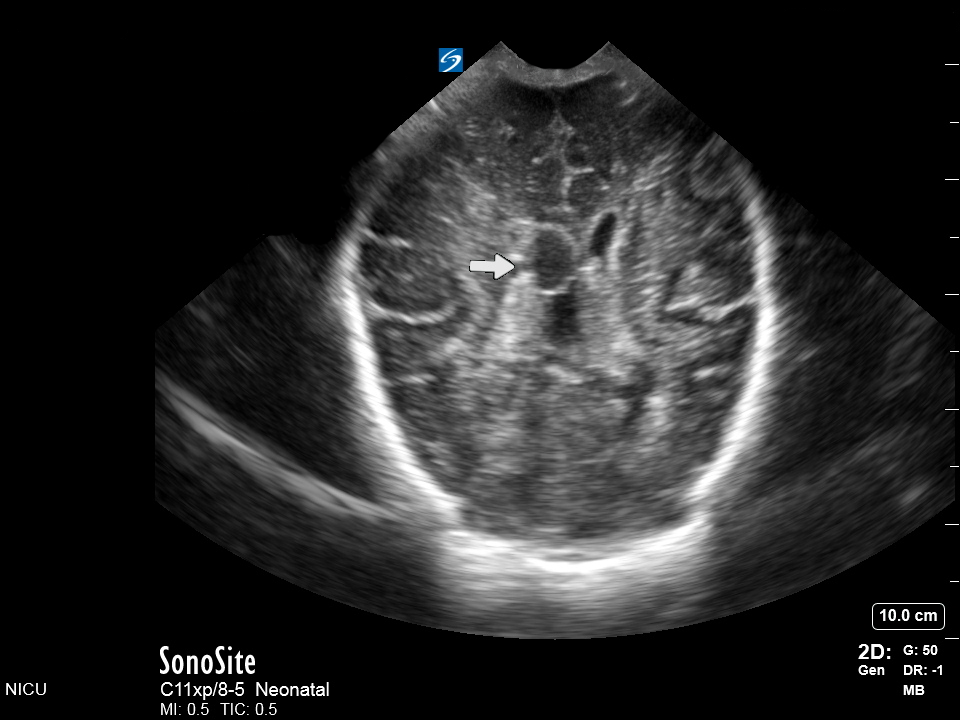

Neonatology Coronal Ventricular and Choroid Plexus View IVH Image